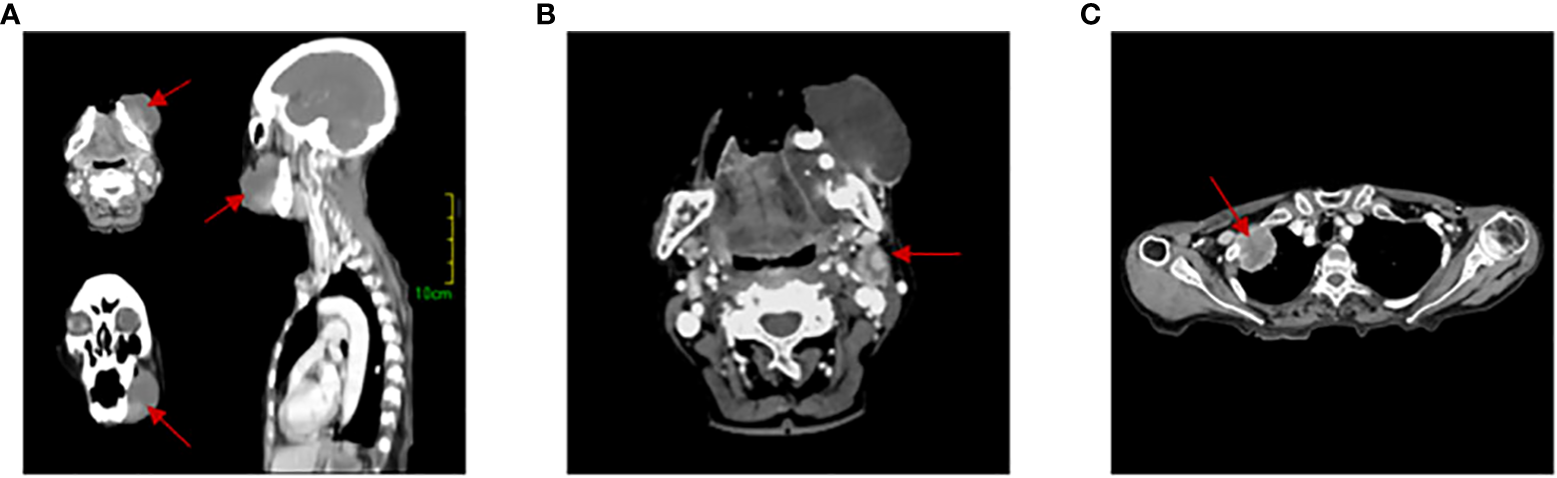

An 83-year-old woman was referred to our hospital with left lower gingival mass for more than 1 month in June 2021. The patient presented with progressive enlargement of gingival swelling and discomfort such as swollen and painful gums and difficulty in opening the mouth for 1 month. The patient was first diagnosed in our hospital, with a healthy past and no special family history. Computed tomography (CT) scan revealed an oval-shaped mass in the left lower gingival area with adjacent mandibular bone destruction and multiple enlarged lymph nodes in the neck and left submandibular area, and an occupying lesion in the upper lobe of the right lung (Figure 1). PET/CT scan showed no other metastases. Physical examination revealed a mass of about 6 cm located in the left lower gingival area, causing difficulty in opening the mouth. Multiple enlarged lymph nodes were palpable in the left neck. According to laboratory testing, red blood cell count was 2.77 × 1012/L, hemoglobin 77 g/L, albumin 32.2 g/L, and the results of the biomarkers CA153, CEA, CA199, CA125, and SCC showed no abnormalities. Histopathological examination revealed an actively growing spindle cell neoplasm, which tends to be a poorly differentiated sarcomatoid variant of squamous cell carcinoma. The pathology of the right pulmonary nodule was confirmed to be metastasis. Immunohistochemistry (Figure 2) outcomes were presented as follows: AE1/AE3 (+), P63 (+), EMA (+), CKpan (+), Vimentin (+), Ki67 (80%), EGFR (70%), S100 (-), CK5/6 (-), P40 (-), CK7 (-), and PD-L1 (DAKO 22C3) (CPS: 50). The patient was clinically diagnosed with cT4aN2bM1 stage IVB gingival carcinoma (according to the AJCC).

Figure 1

Computed tomography (CT) scans. (A) 3D image of gingival tumor. (B) Lymph node metastasis area. (C) Lung metastases lesion. The red arrow indicates the location of the lesion.